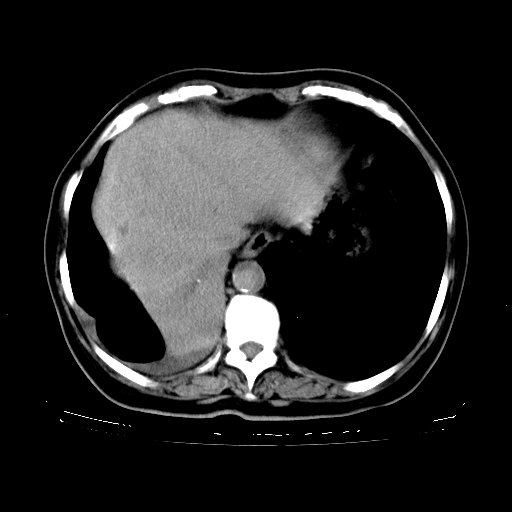

女,70岁,咳嗽、咳痰一个月,低热一周。

1.左上肺结核,部分纤维化。右肺中下叶部分肺不张,内见液化、坏死及点状钙化,右中下叶支气管壁增厚、管腔狭窄,见多个点状钙化,结合临床考虑支气管内膜结核,建议痰检查抗酸杆菌并参考血沉。两肺多个小圆点状高密度灶,境界模糊,多考虑结核肺内播散。但本人年龄较大首先应支气管镜检以除外右肺癌。

2.胸主动脉夹层。

支持,首先一元论解释。胸主动脉部分层面环形低密度,中心强化。环形影不强化。不象真假腔的改变。我考虑动脉炎,不太支持夹层动脉瘤-和大家的观点不一致,希望楼主让患者再做个心血管的彩超吧。